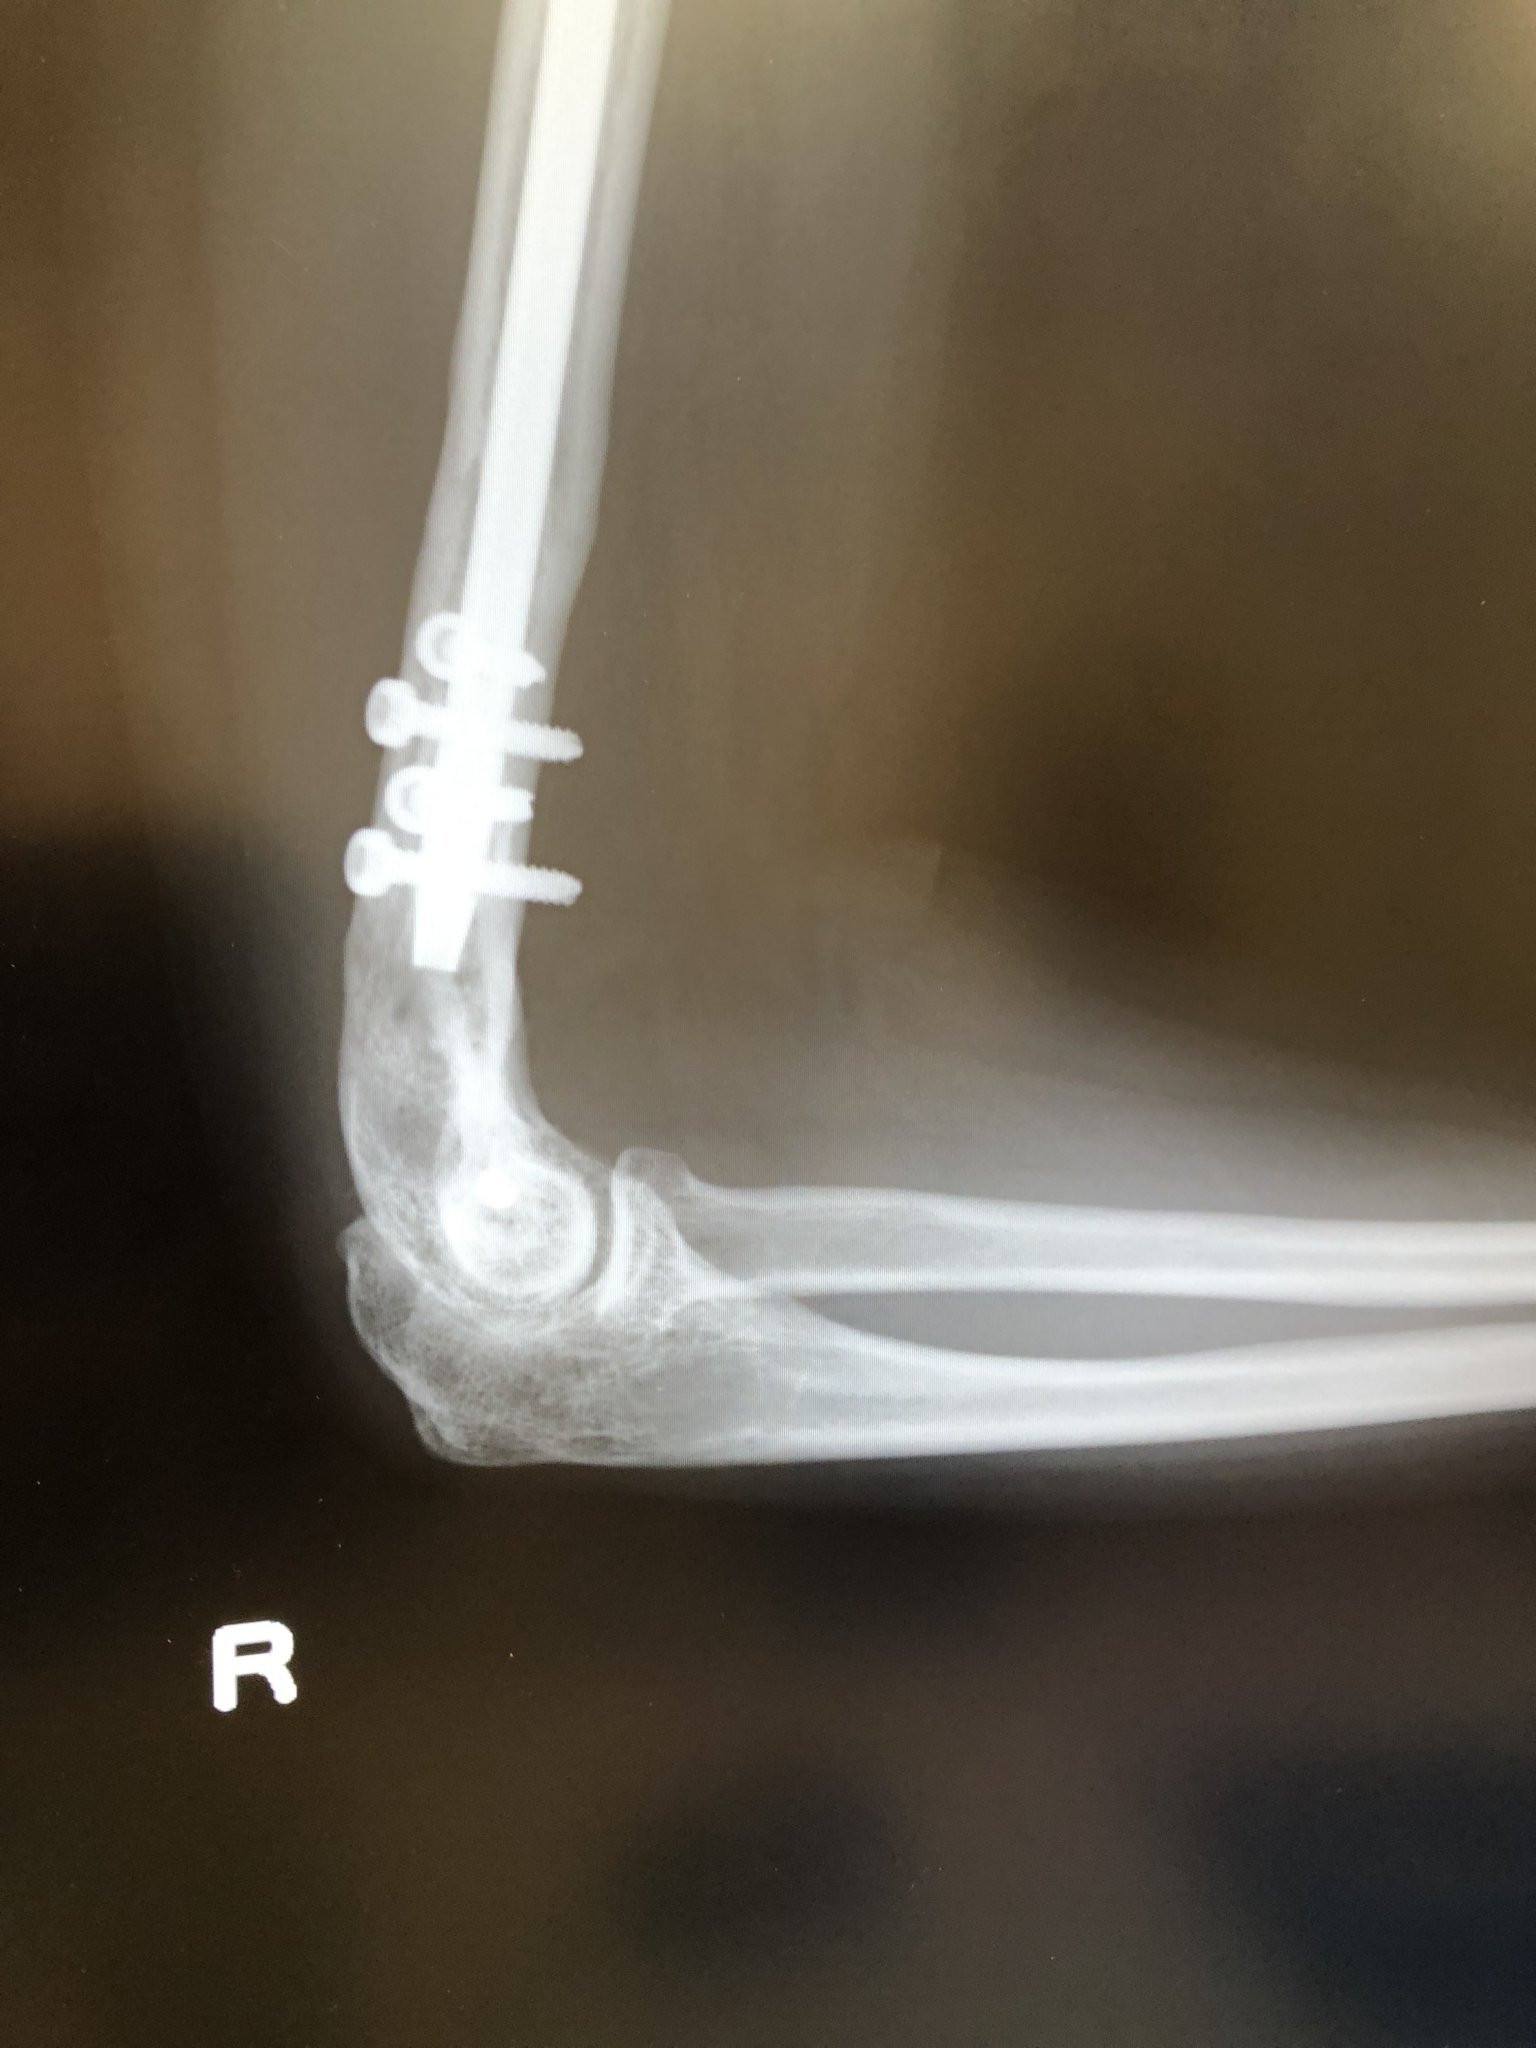

そう、これが私の右腕(^^;;

右腕は機械人間だったんです!